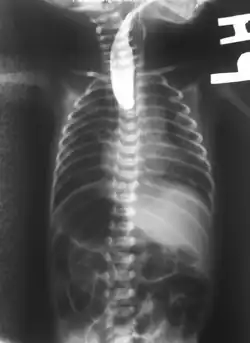

Plain X-ray of the chest and abdomen showing a feeding tube unable to move beyond an upper esophageal pouch.

On plain X-ray, a feeding tube will not be seen pass through the esophagus and remain coiled in the upper oesophageal pouch.[11]

If any of the above signs/symptoms are noticed, a catheter is gently passed into the esophagus to check for resistance. If resistance is noted, other studies will be done to confirm the diagnosis. A catheter can be inserted and will show up as white on a regular x-ray film to demonstrate the blind pouch ending. Sometimes a small amount of barium (chalk-like liquid) is placed through the mouth to diagnose the problems. However, performing such an oral contrast study is not advised due to a risk of aspiration.[30]